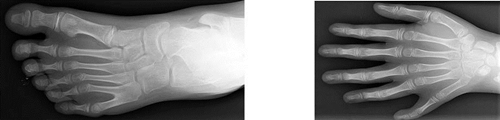

A polidactilia é um exemplo das variadíssimas mutações génicas que se verificam nos seres humanos. Esta anomalia física congénita é caracterizada pela existência, quer nas mãos quer nos pés, de dedos supranumerários (mais de cinco dedos). Habitualmente o dedo extra é uma pequena porção de tecido mole. Ocasionalmente este pode conter osso e raramente, é um dedo completamente funcional. O dedo extra é geralmente uma ramificação anormal de um outro dedo e invulgarmente tem origem no pulso/tornozelo como um dedo normal.

Vulgarmente, o dedo extra situa-se no lado cubital/peronial do membro, menos vulgar é situar-se no lado radial/tibial do membro e raramente se situa entre os dedos centrais. Estes casos são respectivamente a polidactilia pós-axial, a polidactilia pré-axial e a polidactilia central.

Figura 2                                                                                   Figura 3

Polidactilia pós-axial, a partir de                           Polidactilia central, desde do pulso,

uma ramificação.                                               como um dedo normal.